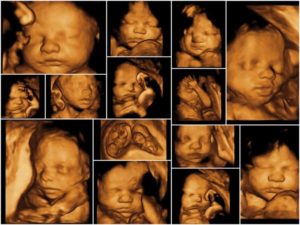

- За счет высокой четкости и полноцветности изображения повышается качество мониторинга – специалист может детально рассмотреть черты лица ребенка, мимические движения, строение позвоночника и конечностей для исключения вероятности формирования пороков и аномалий.

- Подобное знакомство с ребенком в режиме реального времени – трогательный и незабываемый момент для будущей мамы. Качество сигнала позволяет даже распознать эмоции малыша – радость, недовольство или апатию.

- Плод на результатах 4Д УЗ-исследованияПроводить 4D УЗИ при плановом наблюдении беременности целесообразно в период с 20 по 26–29 неделю. Раньше этого срока плод еще не успевает сформироваться настолько, чтобы представлять интерес для видеомониторинга, а с наступлением 30 недели ребенок группируется в матке, принимая закрытую позу, при которой сложно что-либо рассмотреть в деталях.

- Объемное изображение приближено к реальному, с его помощью можно делать даже определение черт лица младенца.

Данный формат, несет информативный характер обследования. Он помогает специалистам увидеть все процессы развития ребенка в трехмерном изображении, а так же его лицо, его мимику.